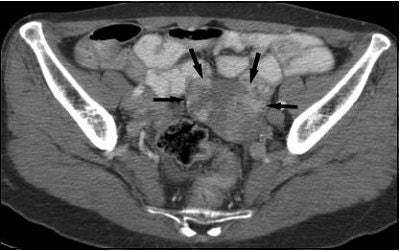

| A 60-year-old woman with unilateral ovarian metastasis from stomach cancer. Contrast-enhanced CT scan showed mainly solid, oval, moderately enhancing mass with smooth margin in left adnexa. Dense enhancing portions (arrows) are evident in mass. Choi HJ, Lee JH, Kang S, Seo SS, Choi JL, Lee S, Park SY, "Contrast-Enhanced CT for Differentiation of Ovarian Metastasis from Gastrointestinal Tract Cancer: Stomach Cancer vs. Colon Cancer" (AJR 2006; 187:741-745). |

According to the imaging findings, ovarian metastatic lesions from stomach cancer were more solid than those from colon cancer, with more prominent enhancement but more discrete enhancement patterns. Ovarian masses from colon cancer tended to be larger, possibly because they are more cystic in nature, the authors stated.